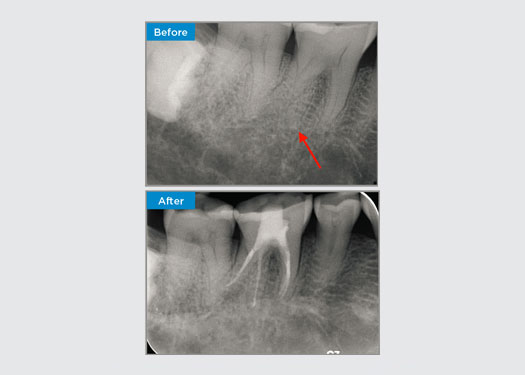

El paciente presentó periodontitis apical asintomática en la pieza dental 34. A partir de la radiografía preoperatoria, se observó que la pieza dental 34 tenía dos raíces visibles. Sin embargo, un escaneo CBCT confirmó un premolar de tres raíces y los canales se dividieron en tres en la raíz media. Una cuidadosa selección de limas es fundamental para este diente delicado.

En esta situación, la preservación de la estructura del diente/raíz es esencial para reducir el riesgo de reborde, transporte, cierre, perforación y fractura de la raíz. La selección de casos, el diagnóstico y la planificación previa al tratamiento son importantes. La selección de limas de endodoncia con flexibilidad, eficiencia y respeto por la anatomía de la raíz natural es fundamental.

El paciente presentó pulpitis irreversible en la pieza dental 46. A partir de la radiografía preoperatoria, la pieza dental 46 se presenta con una raíz distal adicional (morfología dental Radix Entromolaris). Una escaneo CBCT ha confirmado la presencia de raíz distolingual con curvatura grave de la raíz. Una cuidadosa selección de limas es fundamental para esta raíz distobucal delicada.